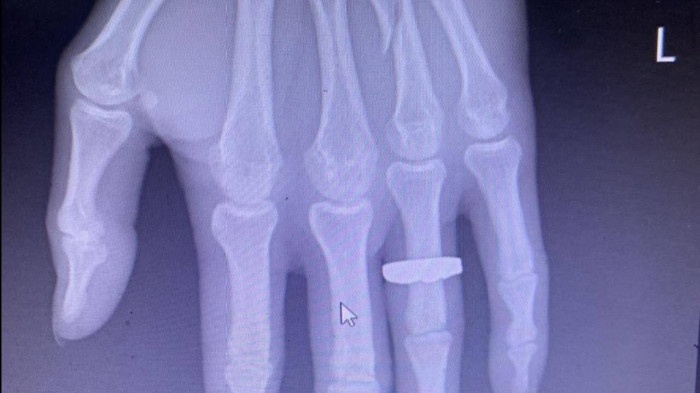

khach bi danh gay tay anh 3

Hình ảnh xương ngón tay áp út bàn tay trái của anh Sáng bị đánh gãy.